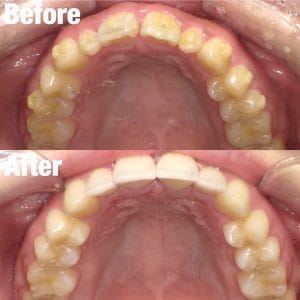

セラミック矯正症例集(ビフォーアフター)

より多くの症例をこちらのページでご紹介しておりますので、合わせてご覧ください

Case033

前歯が虫歯なのと、保険のプラスチックで大きく治療されていて色が悪いこと、歯並びが出っ歯気味であることを気にしてセラミックにしたいという主訴で来院された患者様です。

虫歯が大きかったところは神経治療をきちんと行い、

初診時を含めてトータル4回のご来院で完了です。

今回は前歯を下げる、歯列を整える、白すぎず自然に綺麗に見える色というご希望に沿って治療しました。

ご興味のある方はいつでもご相談ください。

担当 理事長 佐藤 悠野